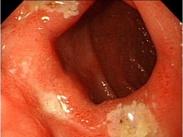

• 病毒性食管炎

628健康網為您分享有關病毒性食管炎的癥狀,病毒性食管炎的治療方法,病毒性食管炎的預防知識,病毒性食管炎的癥狀圖片,病...